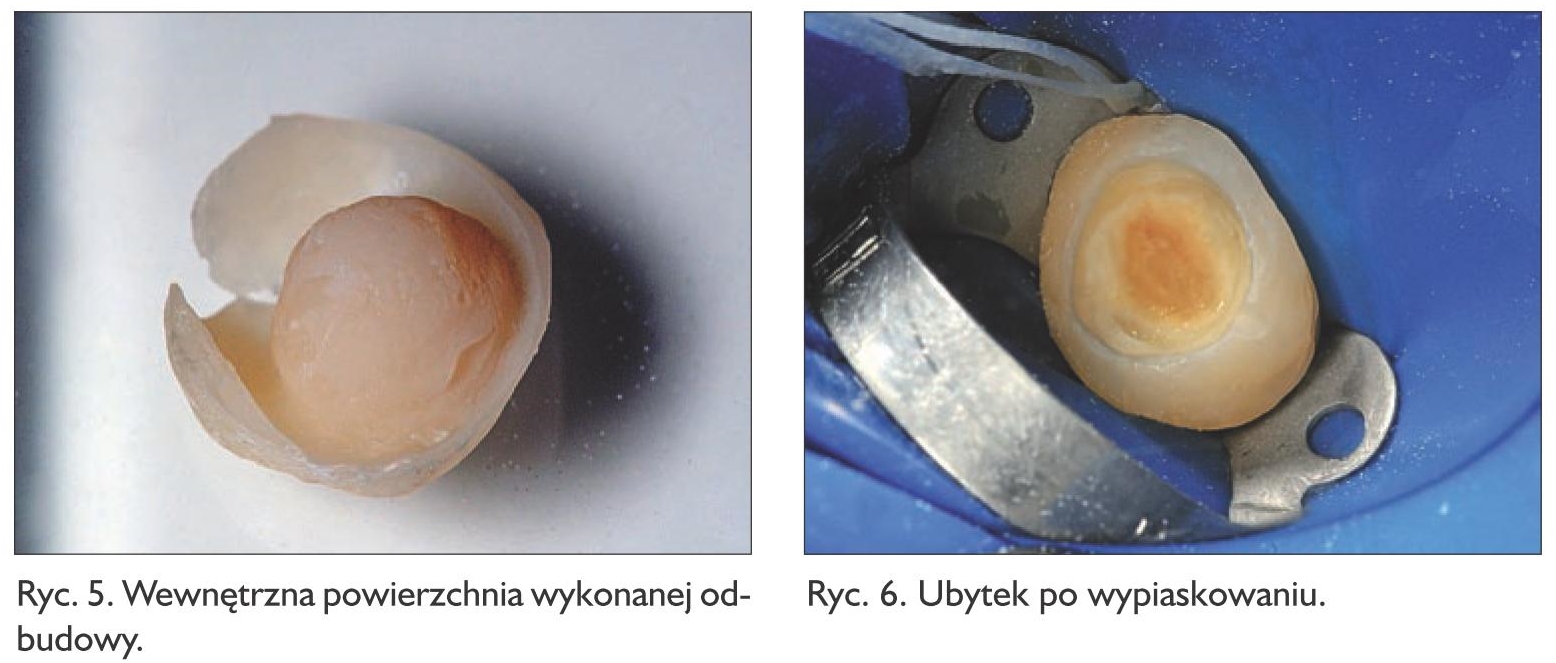

W pierwszym etapie wewnętrzną powierzchnię wypiaskowano mikropiaskarką abrazyjną (MicroEtcher IIa, Danville), używając tlenku glinu o wielkości ziaren 50 μm (ryc. 5). Na tak przygotowaną powierzchnię materiału kompozytowego zaaplikowano na ok. 30 sekund 37% kwas ortofosforowy, który następnie dokładnie spłukano, a pracę osuszono.

Ząb 27 odizolowano od środowiska jamy ustnej za pomocą koferdamu i oczyszczono z resztek żelu glicerynowego. Powierzchnię opracowanego ubytku i otaczającego szkliwa również wypiaskowano, wykorzystując tlenek glinu o wielkości ziaren 50 μm (ryc. 6). Przymierzono wykonaną odbudowę, aby skontrolować jej tor wprowadzania i szczelność. Następnie na powierzchnię wewnętrzną odbudowy i na powierzchnię zęba zaaplikowano samoutwardzalny, uniwersalny system wiążący Tokuyama Universal Bond (Tokuyama Dental), po uprzednim dokładnym wymieszaniu jego składowych – preparatów A i B. Zastosowanie tego systemu eliminuje konieczność odrębnej aplikacji silanu czy dodatkowego primera, daje możliwość przeprowadzenia procedury niezwykle szybko, bez rozgraniczania rodzaju powierzchni, na którą preparat jest stosowany. Dodatkowo system ten nie wymaga naświetlania, a jedynie osuszenia delikatnym strumieniem powietrza na powierzchni odbudowy i w ubytku. Do zacementowania pracy wybrano materiał Estelite Universal Flow (Tokuyama Dental) o konsystencji Medium, w kolorze A3. Kompozyt wprowadzono do ubytku i częściowo na powierzchnię odbudowy, aby mieć pewność, że materiał idealnie zapłynie. Całość nałożono na przygotowany do cementowania ząb, dociśnięto, zebrano nadmiary materiału, a następnie spolimeryzowano. Wykorzystanie do cementowania materiału kompozytowego umożliwia korektę ewentualnych niedokładności lub odpryśnięć materiału w przyszłości. W trakcie dociskania pracy i zbierania nadmiarów materiał doskonale zapływa i daje pewność co do szczelności zacementowanego uzupełnienia. Odbudowę spolimeryzowano światłem lampy polimeryzacyjnej przez min. 60 sekund z każdej strony. Zdjęto koferdam, a następnie usunięto pozostałości żywicy kompozytowej.